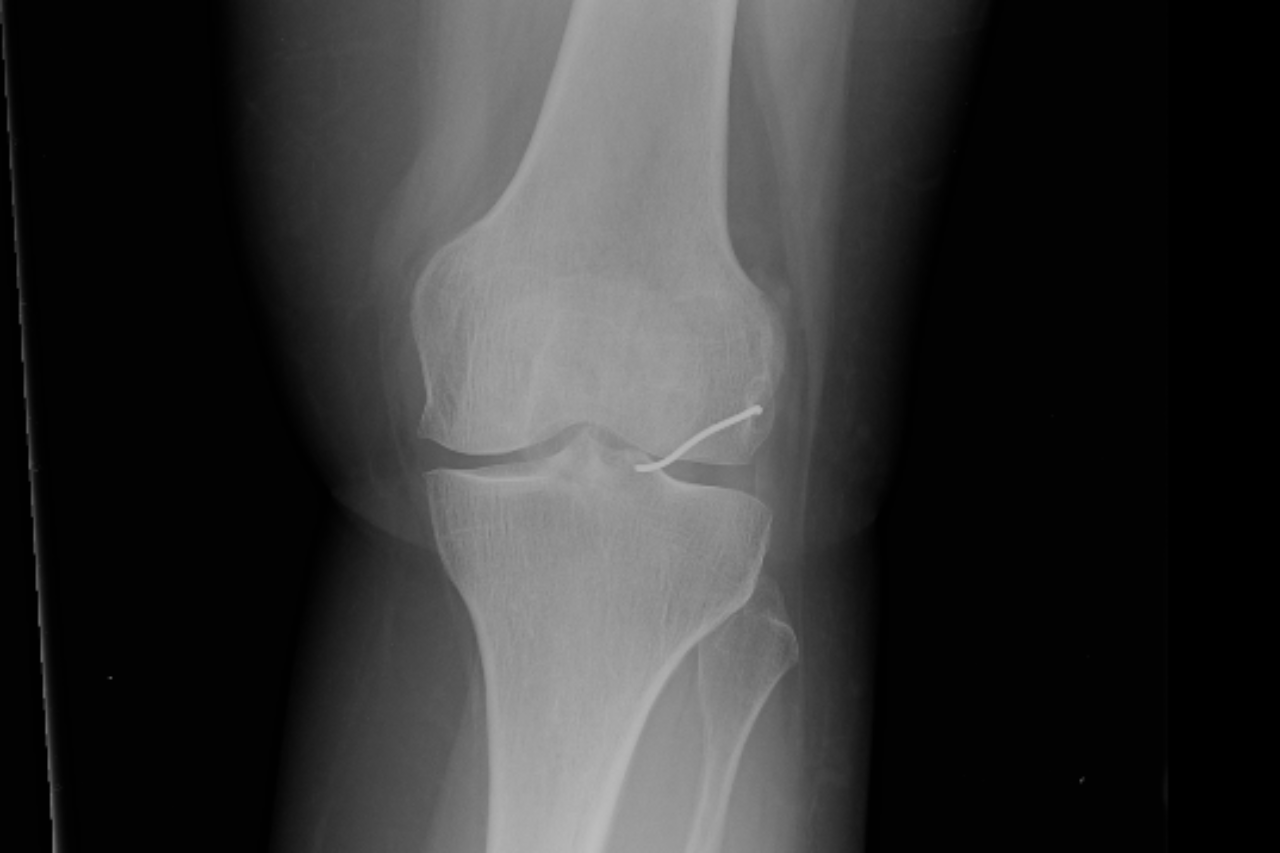

כעבור כשנתיים, ולאחר שספגה מהלומה באזור הברך, החלה האישה לסבול מכאבים עזים ונבדקה על ידי אורתופד. זה שלח אותה לצילומי רנטגן, וגילה, למרבה ההפתעה, כי בברך ישנה פיסת מתכת, והיא זו שככל הנראה גרמה לכאבים. האישה הופנתה לניתוח, שלישי במספר, ובמהלכו הוצא מברכה תיל מתכת באורך 3.5 ס"מ.